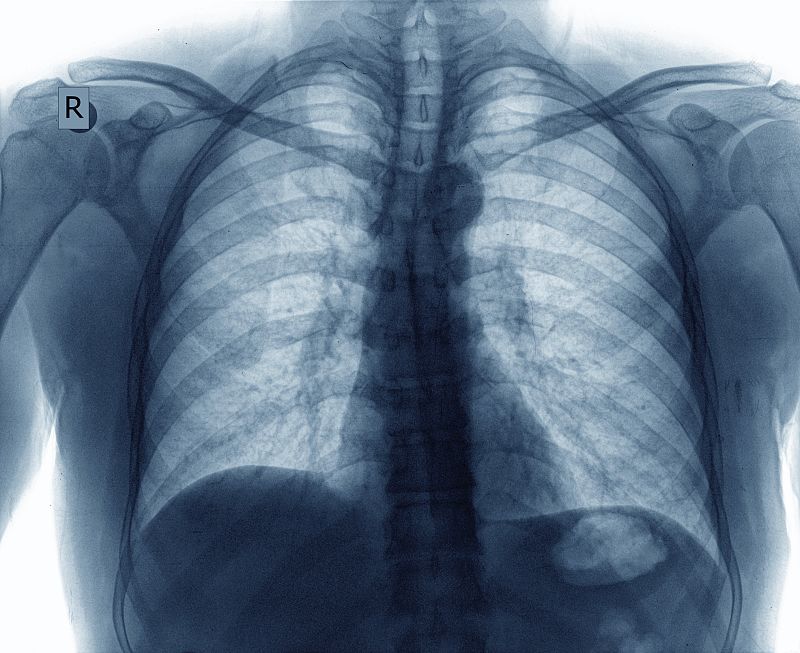

Ahora, investigadores del Centro Nacional de Investigaciones Oncológicas (CNIO), han demostrado que la combinación del acortamiento de los telómeros y las agresiones ambientales desencadena fibrosis pulmonar idiopática, una enfermedad en la que el tejido del pulmón va desarrollando cicatrices que lo vuelven rígido y dificultan la respiración.

La fibrosis pulmonar idiopática (FPI), que afecta a unas 8.000 personas en España, provoca una pérdida progresiva de la capacidad respiratoria y puede ser letal en pocos años, ha informado el CNIO en una nota.